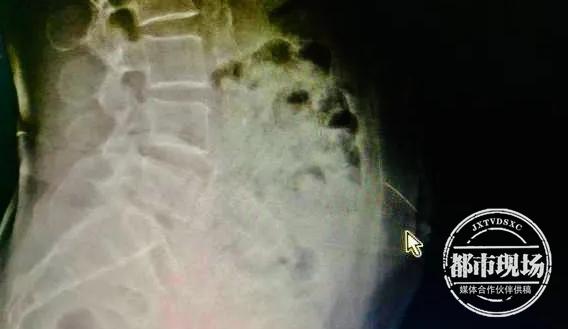

入院后,医生第一时间通过拍片发现,针还在梁婆婆腹壁里。由于针灸用针又细又长,稍有不慎可能扎到腹腔内脏器,带来严重危害。为了确认针的位置,尽快把针取出,医生对患者做了CT定位和三维重建,发现针已从皮下组织扎到了腹直肌里,万幸未伤及内脏。

确定针的位置后,医生迅速为梁婆婆施行介入手术,通过垂直面向下切开2厘米,成功将断针从腹中取出。随后,医生还给梁阿婆打了破伤风针。